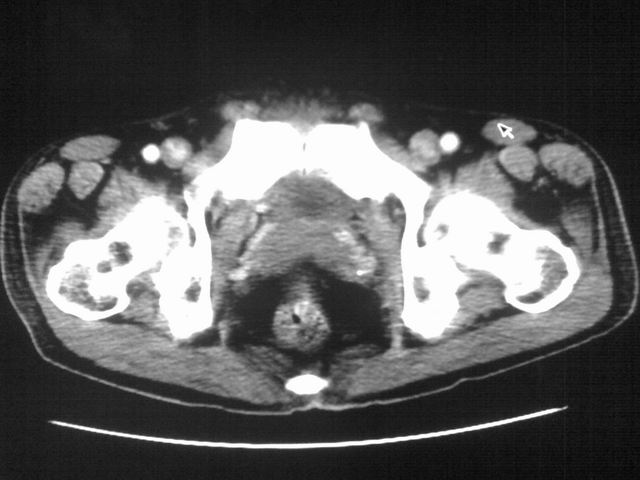

患者m 56岁,盆腔及下腹部胀痛半年,加重1月余,消瘦\中重度贫血.(附:平扫时直肠的高信号为,残留的钡剂).补一下病史:胃镜及纤维结肠镜均无明显异常.

首先是病灶的定位,平扫看很象肠管肿瘤但既然纤维结肠镜正常就可以除外结肠病变,增强成不均匀强化,位于右下腹部应该首先考虑回肠末段占位性病变,1淋巴瘤,2间质瘤,3腹膜后神经原肿瘤待除外,

膀胱后方及直肠前方见巨大混杂密度影,与前列腺相连且向膀胱内突入,精囊腺显示不清;考虑前列腺癌侵犯精囊、膀胱。

膀胱及直肠间有不规侧的软组织密度影,内密度不均匀。其内有坏死囊变,前列腺及精囊腺,膀胱后壁受浸。结合病史考虑腹膜后肉瘤可能性大。